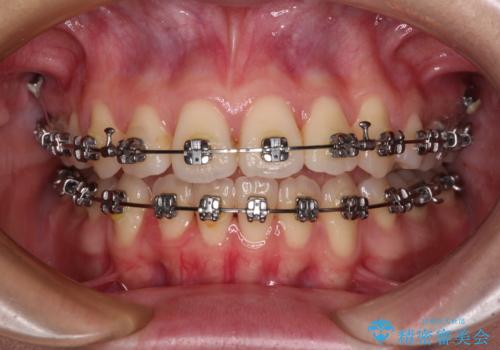

- メタルブラケット

- 1年6ヶ月

舌の突出癖によるオープンバイトになっていたため、インビザラインによるマウスピース矯正をおすすめしましたが、自己管理の自信がないとのことで、ワイヤー装置による矯正治療を行うこととしました。

舌の突出癖が認められると、上下前歯の隙間を閉じることができません。

舌のトレーニングをしっかりと行っていただくことで、歯列を整えることができます。